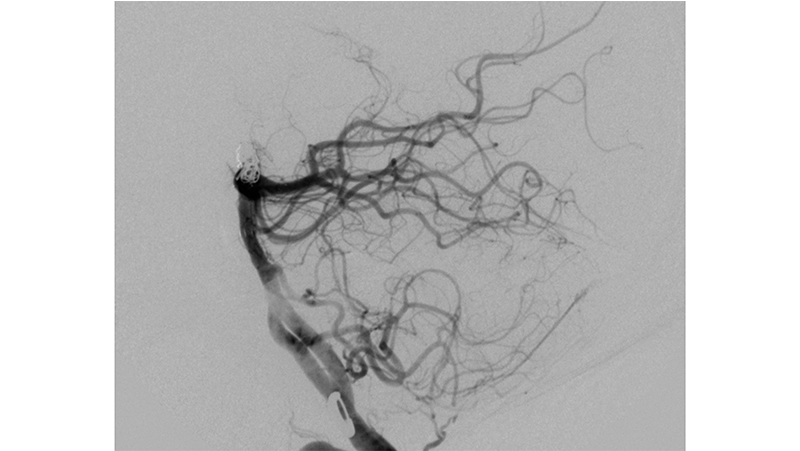

Εικόνα 2: Στην προκειμένη περίπτωση, λόγω της μορφολογίας του αυχένος, θα χρησιμοποιηθεί η τεχνική του Y-stenting όπως φαίνεται στην παραστάση virtual stenting του αγγειογραφικού μηχανήματος.